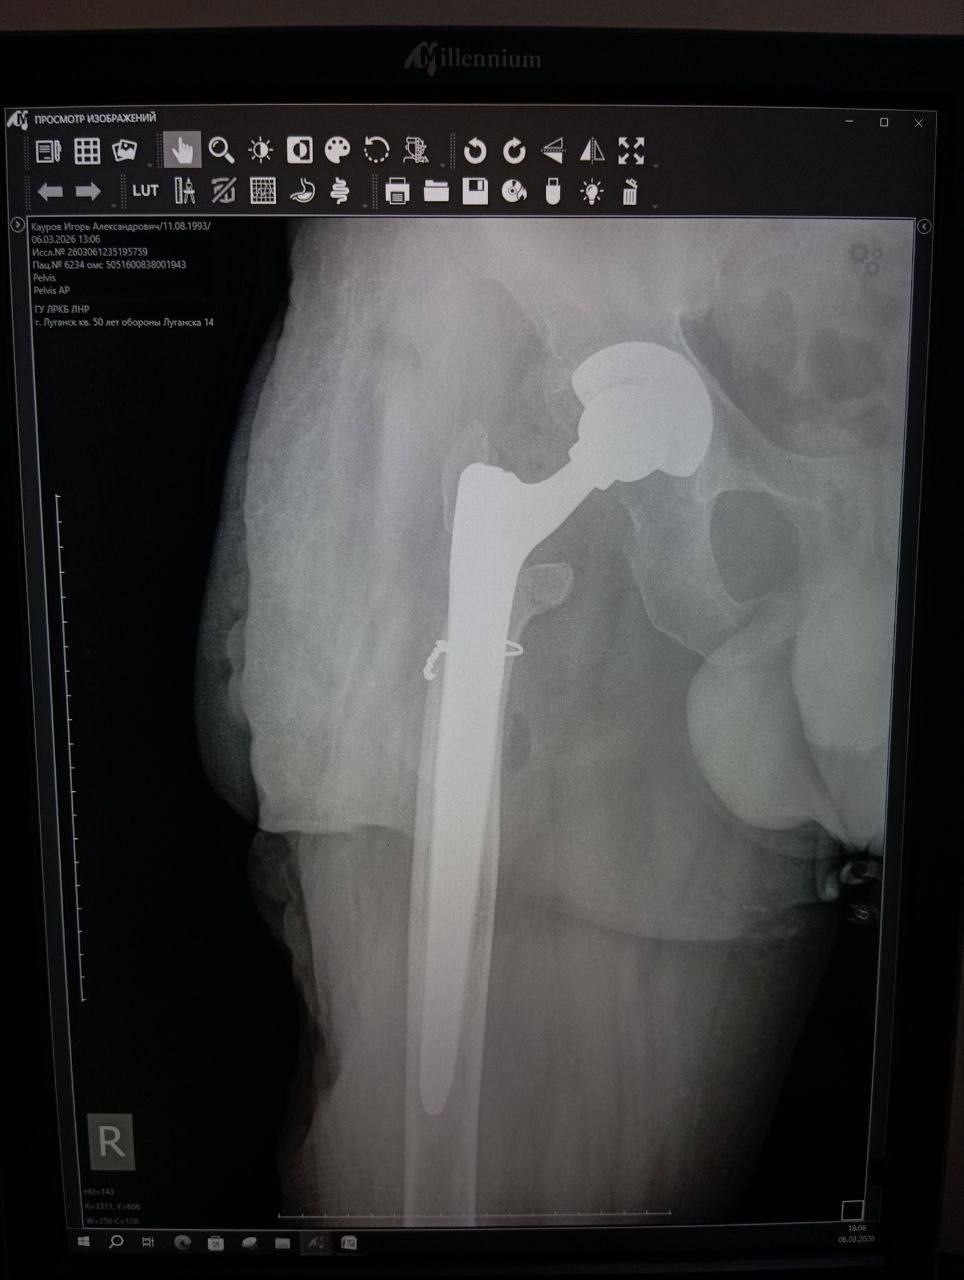

Впервые в ЛНР проведена сложнейшая операция по эндопротезированию тазобедренного сустава с использованием ревизионных систем.

При помощи новейших технологий врачи смогли компенсировать укорочение конечности на 8–9 сантиметров и вернуть пациенту возможность ходить без хромоты.

Хирургам ЛРКБ предстояло работать в рубцово-изменённых тканях после десятка предыдущих вмешательств, устранить очаги инфекции и с помощью специальных ревизионных компонентов восстановить биологическую ось конечности и вернуть ей физиологическую длину.

Операция прошла успешно. Для ветерана, награждённого медалью «За отвагу», это шанс избавиться от боли и хромоты, вернуться к полноценной жизни. Впереди — курс реабилитации.